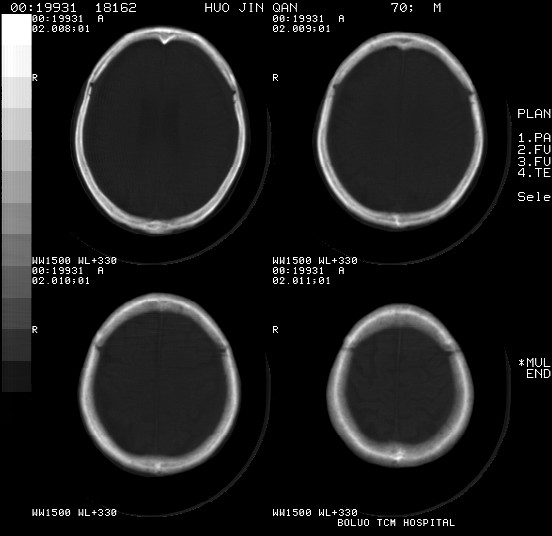

以下是引用随光逐影在2008-3-25 20:15:00的发言:[br]双侧额颞顶部亚急性(或慢性)硬膜下血肿。

以下是引用liuyue在2008-3-26 18:57:00的发言:[br]以下是引用随光逐影在2008-3-25 20:15:00的发言:[br]双侧额颞顶部亚急性(或慢性)硬膜下血肿。 [br]支持![br]可以无明显外伤病史,老年人可以在激烈摇晃或轻微头部碰创头部时,发生硬膜下出血.